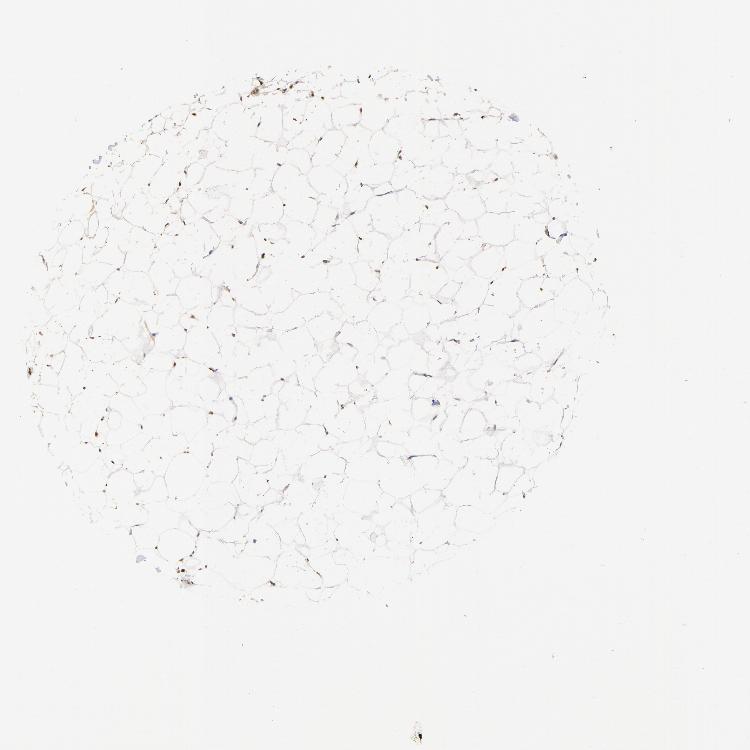

ADIPOSE TISSUE - Antibody stainingi

Antibody staining in the annotated cell types in the current human tissue is reported as not detected, low, medium, or high, based on conventional immunohistochemistry profiling in selected tissues. This score is based on the combination of the staining intensity and fraction of stained cells.

Each image is clickable and will lead to virtual microscopy that enables deeper exploration of all samples and also displays staining intensity scores, fraction scores and subcellular localization as well as patient and tissue information for each sample.

Antibody HPA003358

Adipocytes High